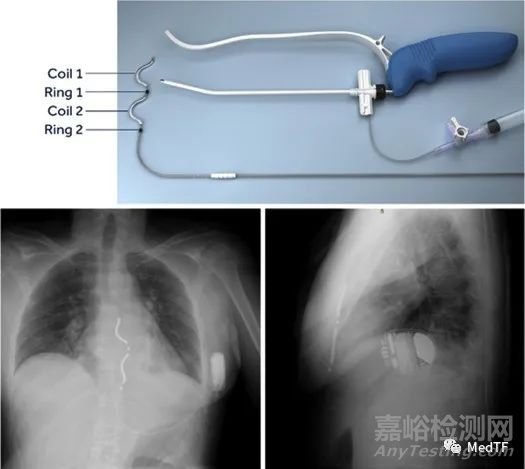

EV ICD導線為ε形,具有2個起搏/傳感電極和2個除顫線圈段(每個4厘米),為了除顫目的將其綁在一起以形成一個8厘米的整體除顫線圈。EV ICD中有3個傳感和3個起搏向量可用。感測矢量包括2個環(huán)形電極之間的近場矢量和從每個環(huán)形電極到ICD裝置的2個遠場感測矢量。起搏向量包括環(huán)到環(huán)向量、線圈到線圈向量以及從遠端環(huán)到近端線圈段的向量。